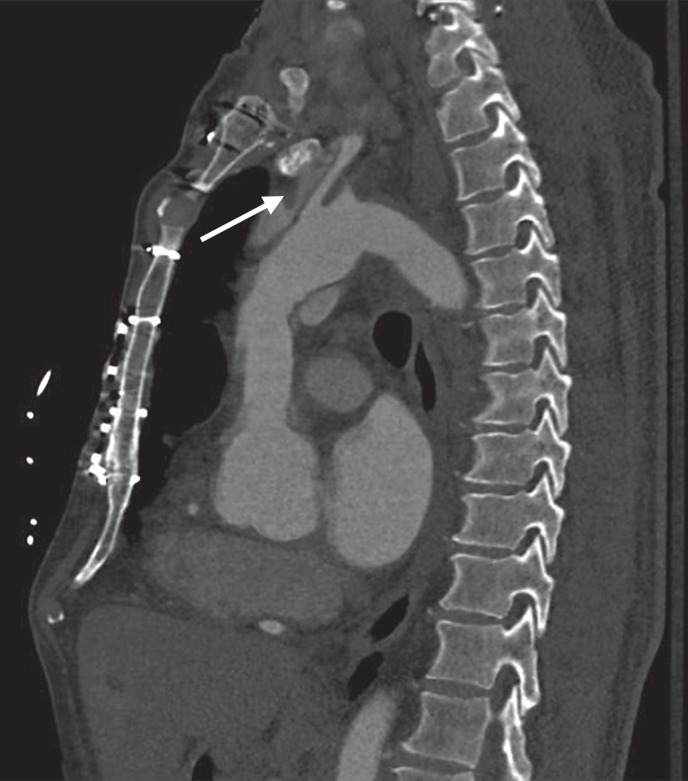

Case presentation: We report a patient with a chronic Stanford type A aortic dissection with dissection extension into the left common carotid artery and left internal carotid artery who had a good clinical outcome following mechanical thrombectomy for a symptomatic middle cerebral artery occlusion. We also review other cases in which endovascular mechanical thrombectomy was conducted in patients with aortic dissection and acute ischemic stroke and discuss the potential risks and benefits of carotid artery stenting in this clinical situation.